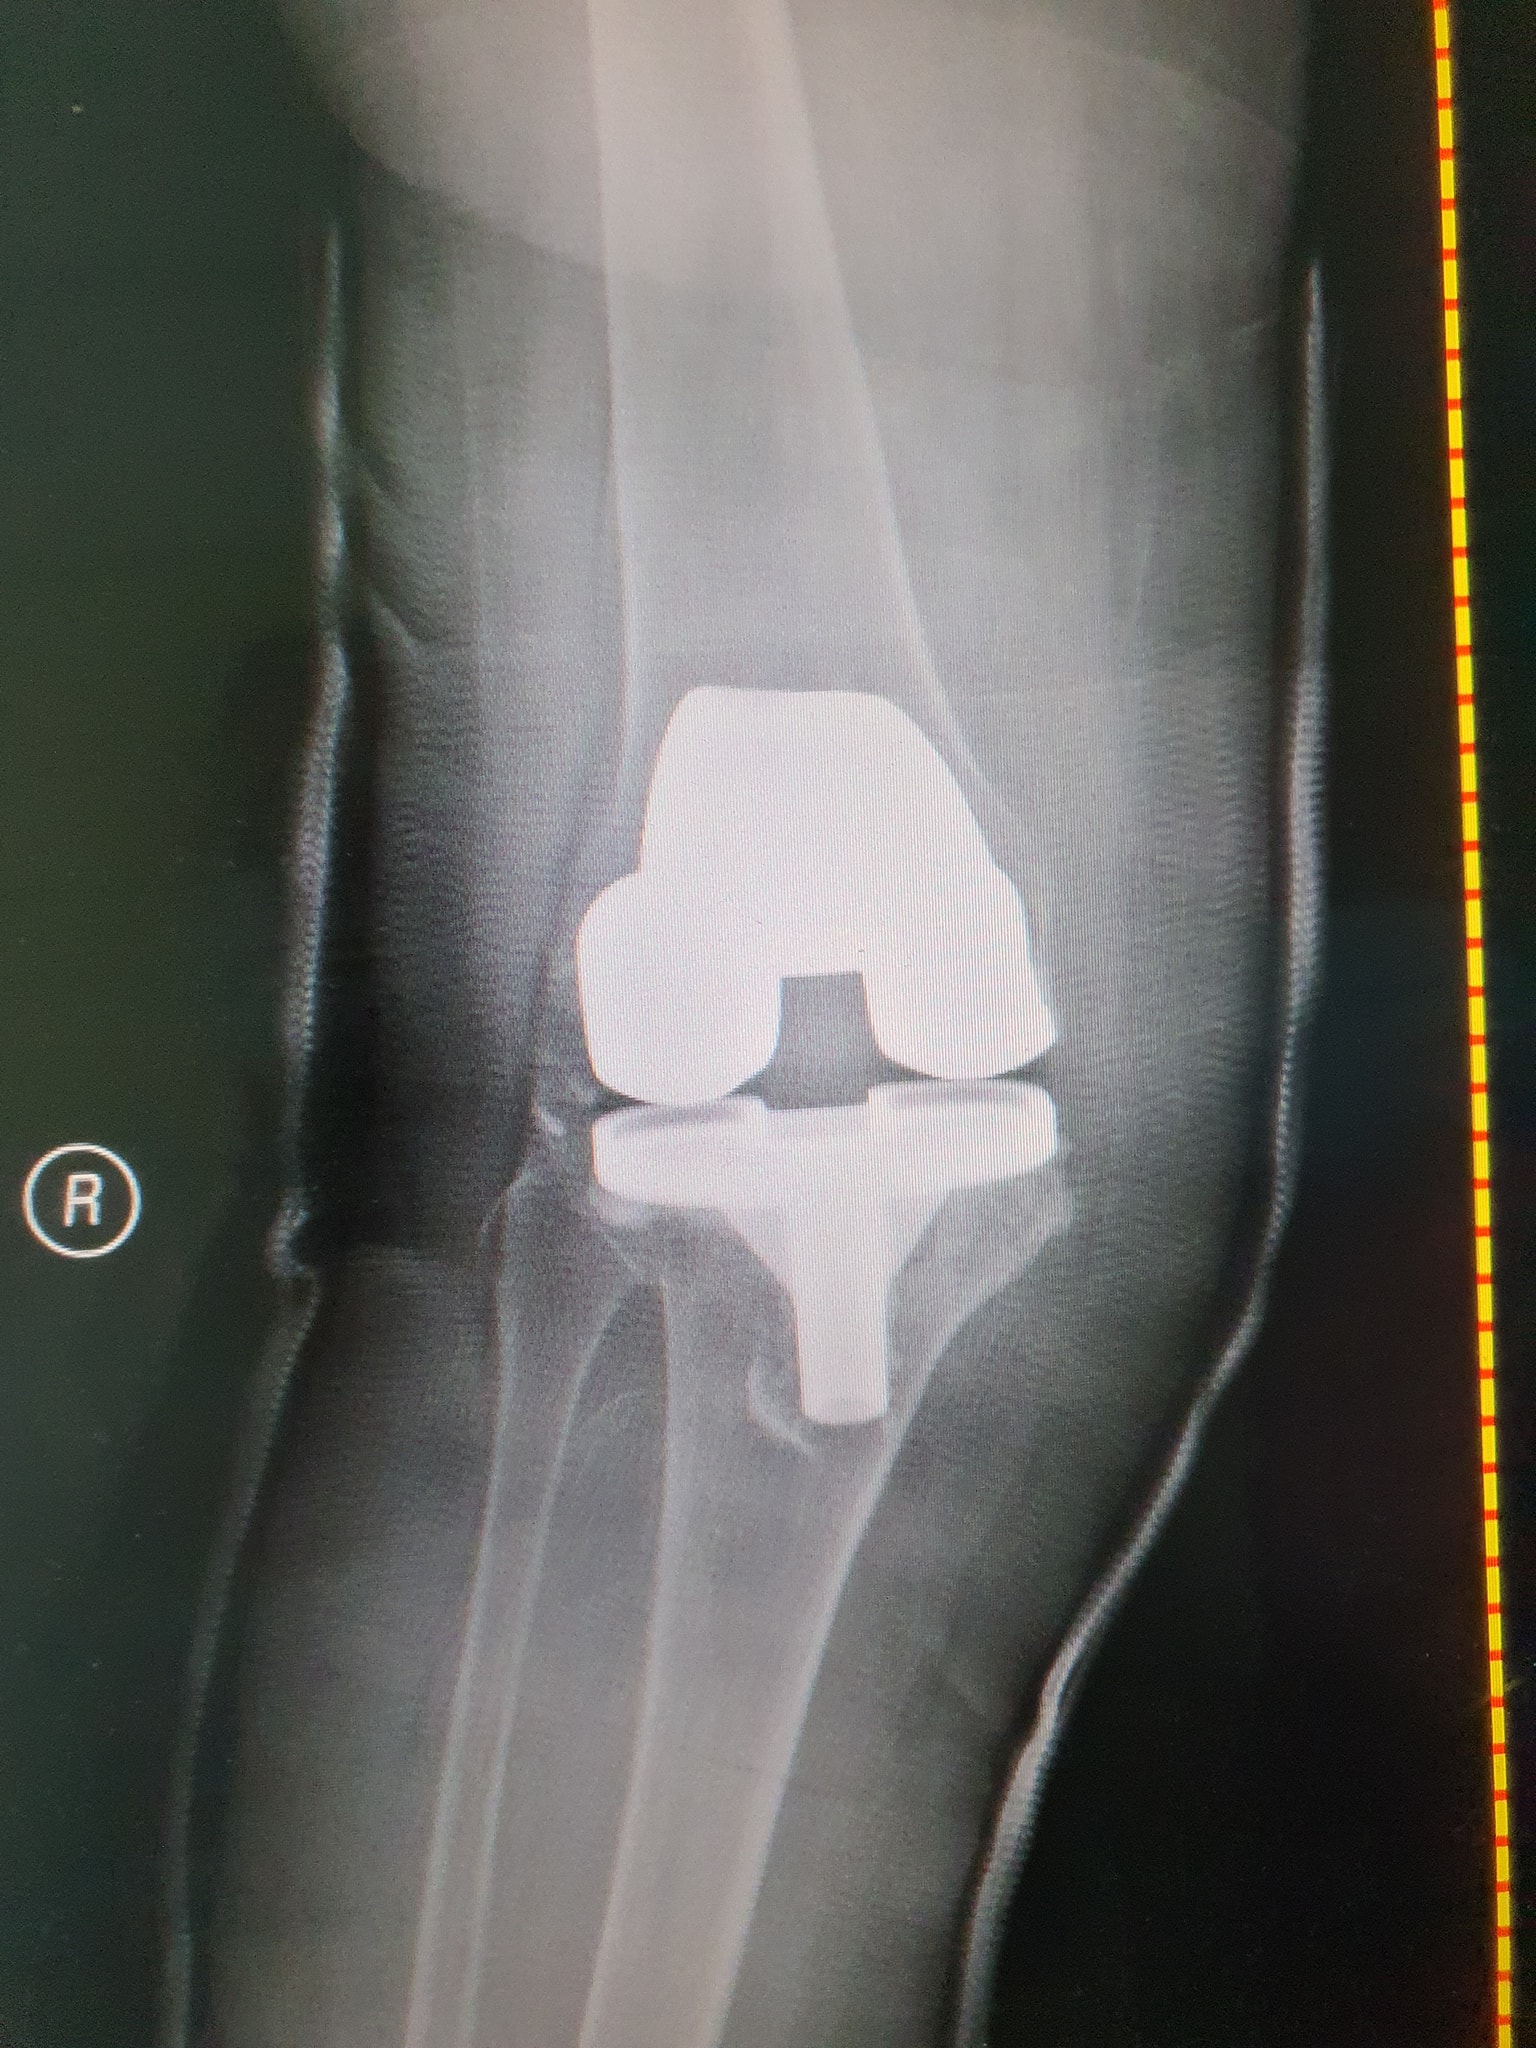

زراعة المفاصل الصناعية ورك و